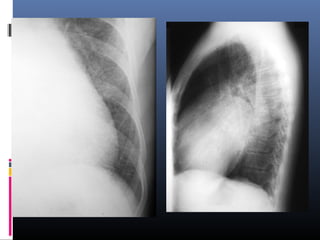

“SIGNO DE LA SILUETA”

Hecho que cualquier opacidad intratoracica, si

esta en contacto con el borde del corazon, de

la aorta o del diafragma lo borrara, mientras

que una lesion intratoracica que no esta en

contigüidad con el borde de una de estas

estructuras no oblitera su borde.

1.Cuando una lesión alveolar borra el borde

cardiaco, parcial o totalmente, su localización es

anterior, y por lo tanto tiene que estar en el

lóbulo medio, lingula o segmento anterior del

lóbulo superior

2. Cuando una densidad se superpone al

borde cardiaco y no lo borra, esta situada

en el lobulo inferior, aunque tambien las

lesiones del mediastino posterior y de la

cavidad pleural posterior pueden

presentar la misma imagen.22

33

3. Cuando el borde derecho de la aorta

ascendente esta obliterado, la lesion esta

situada en el segmento anterior del lobulo

superior derecho o en el lobulo medio

55